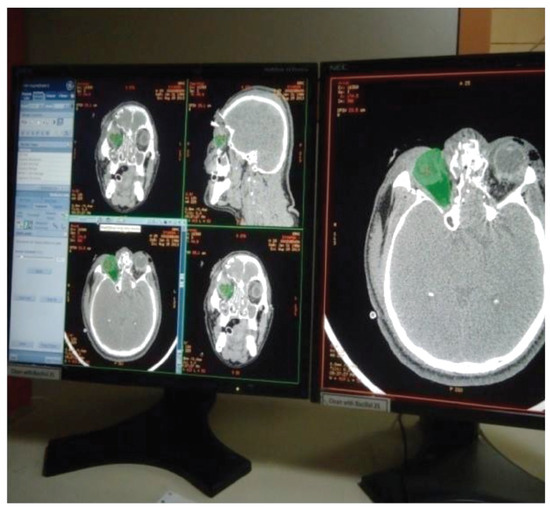

Figure 1.

Mapping the orbital content with marker in continuous axial, sagittal, coronal sections.

Figure 2.

Using CT-VCT 64 slice XT console, preand postoperative CT [12] scans were done for the patients with 120 kV, 250 mA, and slice thickness with appreciation of 2 mm. Retro reconstruction was done at 0.625 mm in a bone window of window width 2,000 and window length 350: soft-tissue window of window width 300 to 350 and window length 100 in an advance workstation ADW 4.4. The anterior border of the orbital floor was determined using first CT slice and the posterior border is the apex of orbital cavity. Orbital volume [13] is measured in axial, sagittal, and coronal sections (Figure 1 and Figure 2) by selecting mapping tool provided with the software of computer program, and orbital volume within the bony borders is mapped in every slice to calculate the orbital volume automatically displayed on the monitor (Figure 3, Figure 4 and Figure 5) after the end of mapping.